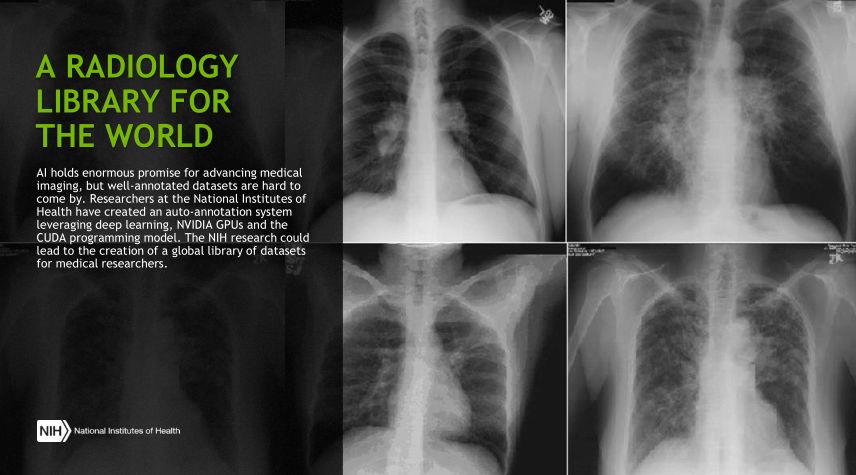

这张图展示的是一个library,即医学图像数据库,医学图像由于其敏感性和工作量,正规的注册数据集很难得到,但在诊断和治疗中非常关键, 是美国的国立研究院提出的一个注册系统,其实这就是一个获得数据集的方法。